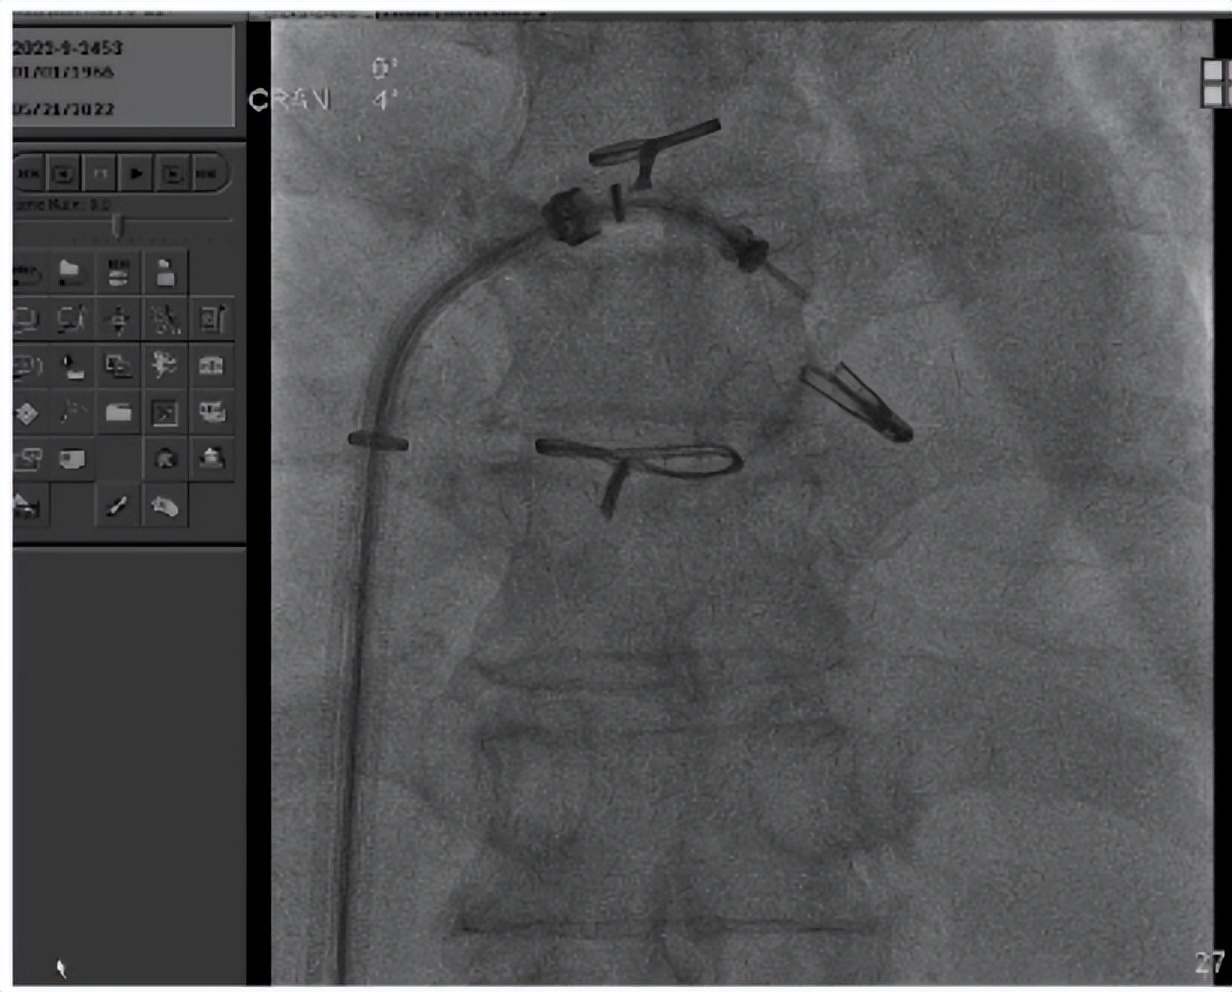

全麻状态下陈魁主任手术团队(图四)经右侧股静脉穿刺,通过MitraClip®独特的三层双调弯设计,经房间隔穿刺顺利将导管送入左心房和左心室,到达二尖瓣膜目标位置调整角度抓取瓣叶(图五)。随后,术者精准对位释放MitraClip®夹合器,准确捕获并固定(图六),“缘对缘”技术使二尖瓣由大的单孔变成小的双孔,位置精确(图七)控制返流且无瓣口狭窄(图八),血流动力学明显改善,手术取得圆满成功。

图五(瓣下调整角度并成功夹取瓣叶)

图六(MitraClip关闭双臂,稳定地固定住瓣叶)

图七(MitraClip稳定于病变位置)